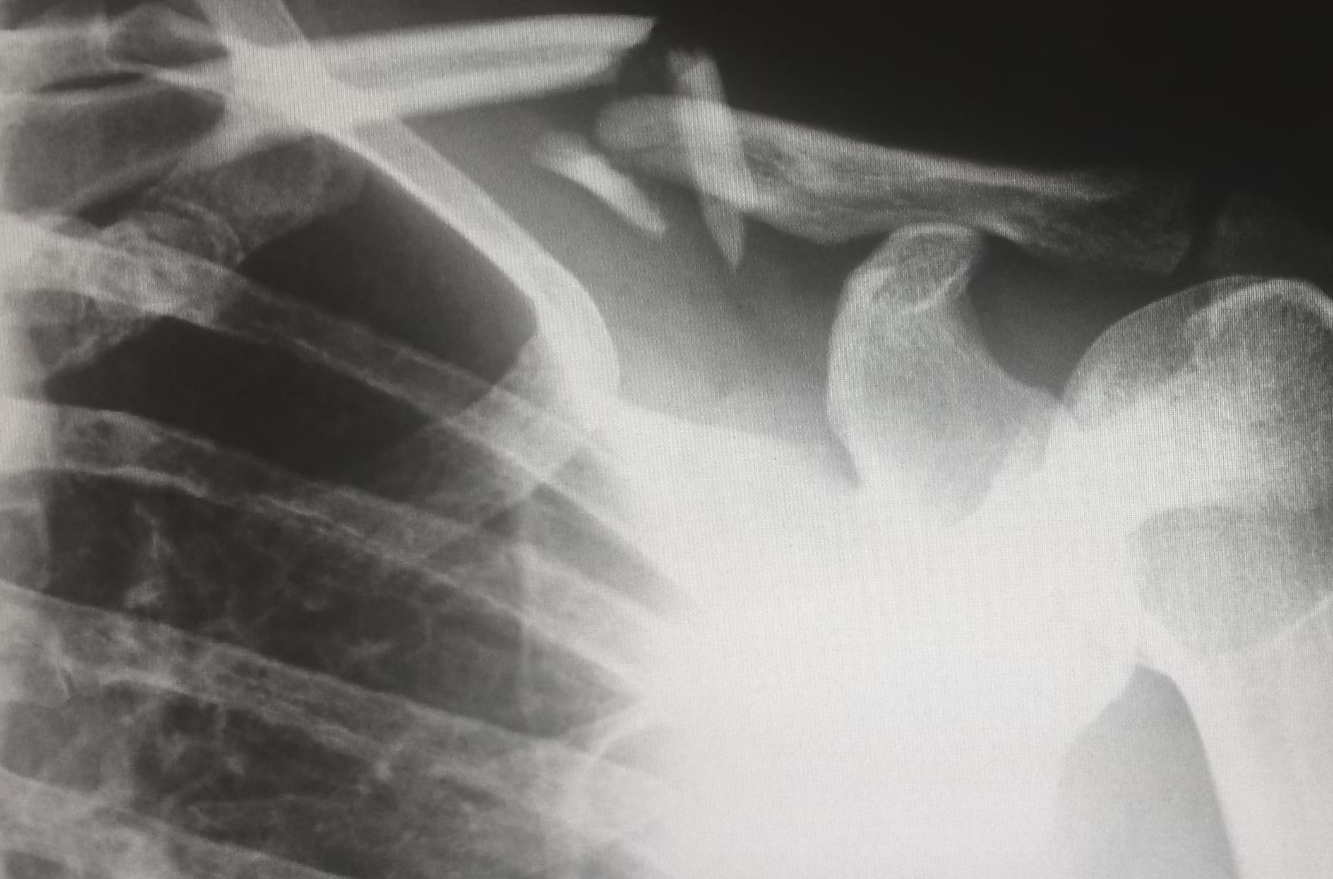

흉부 엑스레이

폐 건강을 확인하는 검사로, 폐렴, 결핵, 폐암 등의 질환을 조기에 발견할 수 있습니다. 흉부 엑스레이는 특히 흡연자나 폐질환 위험이 높은 사람들에게 필수적인 검사입니다.